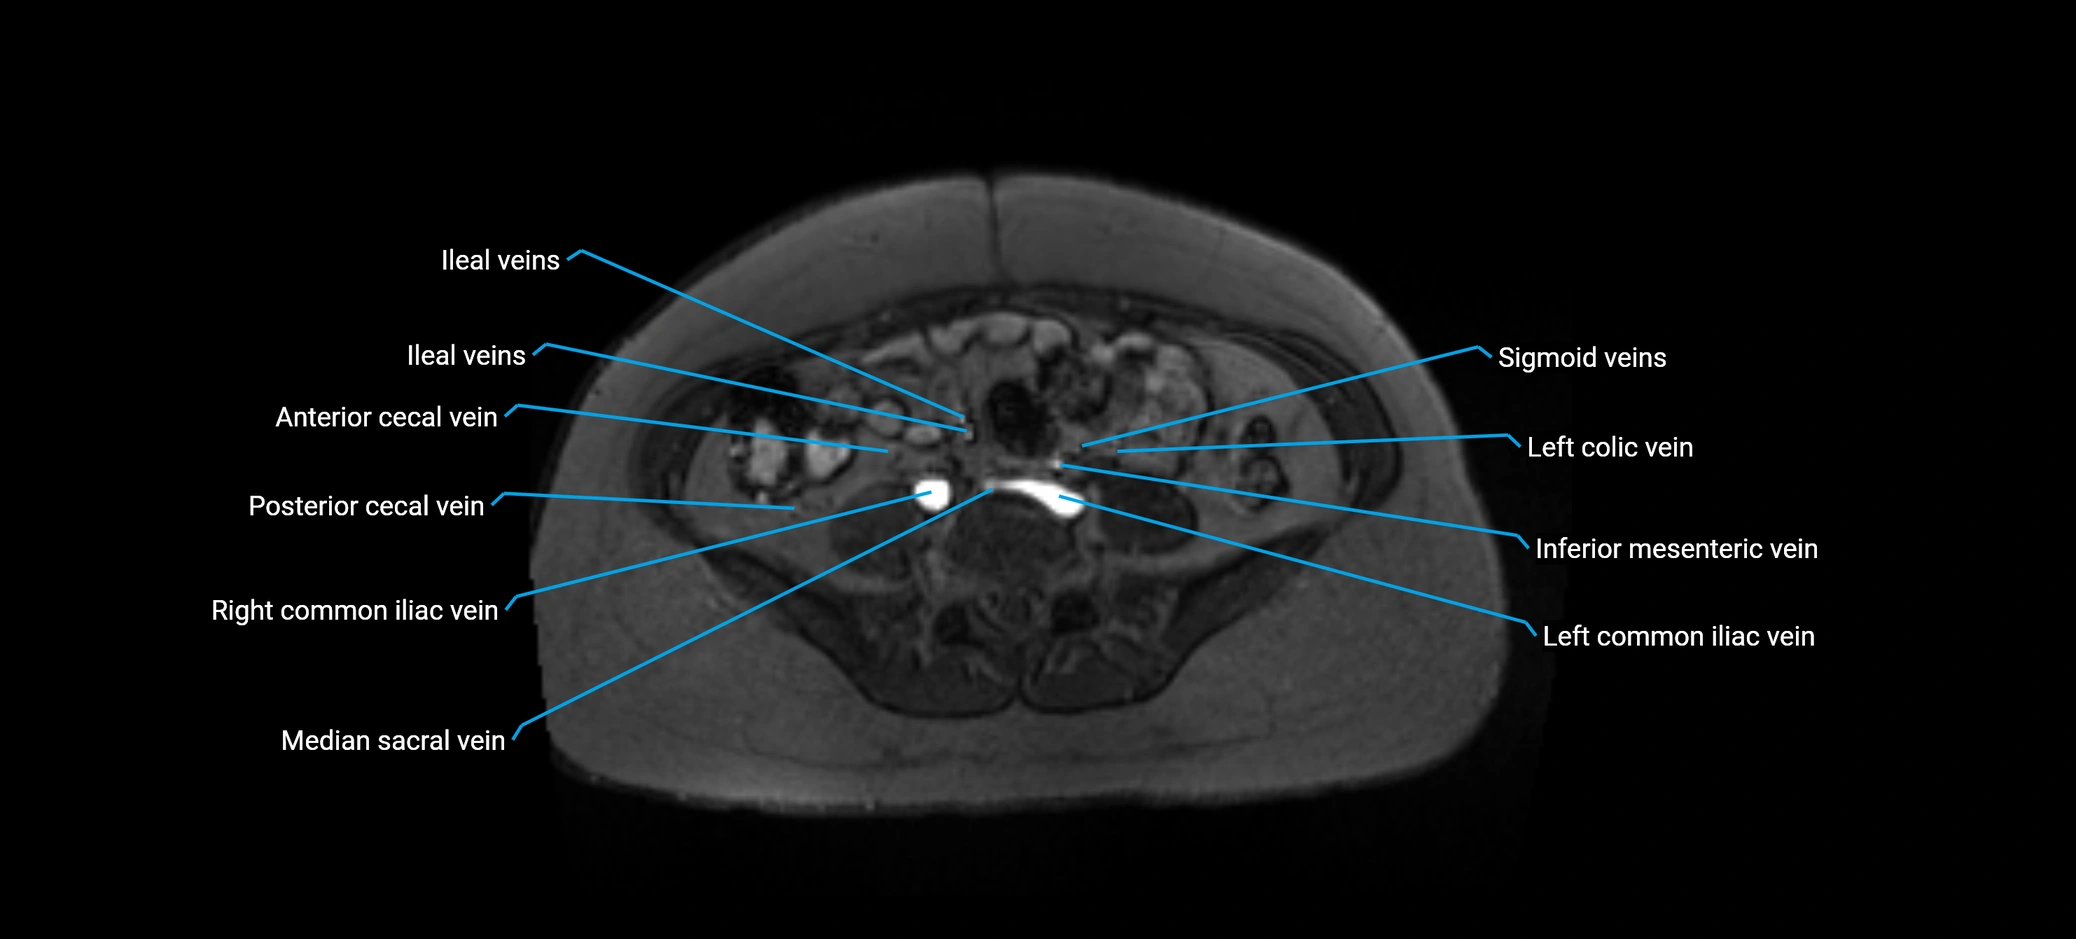

MRI image

image